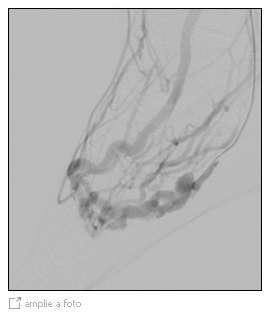

Embolização de malformação Arteriovenosa (MAV)